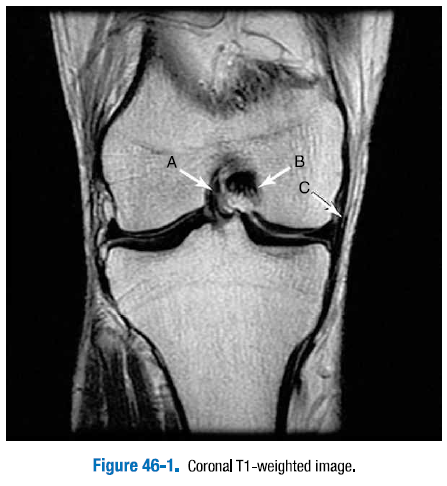

3. 그림 46-1 ~ 그림 46.4에 있는 무릎의 표지된 정상 구조물을 확인하라.

A. 전방십자인대   B. 후방십자인대   C. 내측측부인대

D. 내측 슬개골지대   E. 내측광근

F. 전방십자인대   G. 후방십자인대   H. 슬개골건   I. 대퇴사두근건

J. 외측반월판 전방각   K. 외측반월판 후방각   L. 슬와근건